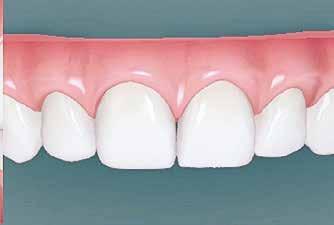

A hiányzó oldalsó kismetszők részárással történő kezelése során a szemfogak és oldalsó fogak meziális mozgatása közben a fogszabályozó orvosnak csiszolással kell a fogak formáját igazítani. Már a kezelés elejétől a szemfog elcsiszolása nem csak az incizális részre kell hogy kiterjedjen, hanem az approximális, palatinális és a vesztibuláris felszín éli negyedére is. Így érhetünk el egy rövidebb klinikai koronát, a vesztibulo-orális méret csökkenését, egy incizális élet, valamint a szemfog megfelelő pozicionálását a kismetsző helyén. A túl széles szemfog megakadályozza a megfelelő interkuszpidáció kialakítását az oldalzónában. A palatinális felszín elcsiszolásával biztosítjuk az interferenciák nélküli metszővezetést, és a megfelelő overjetet a frontfogak enyhe érintkezésével. Ha a szemfogra a későbbiekben esztétikai pótlás készül, a megfelelő approximális elcsiszolás (az esztétikai fogorvossal történő egyeztetés után) biztosítja a zenith kívánatos pozícióját a későbbi felépítéshez. A mezializált kisőrlő palatinális csücskének elcsiszolására csak akkor van szükség, ha ez akadályozza a megfelelő fogérintkezést. Az első kisőrlő mindkét csücske fontos a már a szemfog helyén álló fog esztétikai és funkcionális beállításához.

A szemfog oldalsó kismetsző helyére történő bemozgatása során a fog átalakítása javasolt a két fog eltérő morfológiai adottságai miatt (1. a-b. ábra). A fog kontúrozása, vagy úgynevezett formázása magába foglalja az approximális felszínek elcsiszolását, valamint a többi fogfelszín igazítását a kívánt fogformának megfelelően [1].